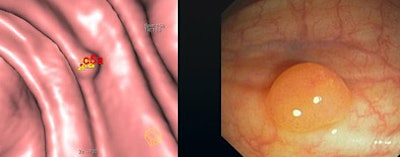

![]() |

| CAD performed best in the detection of medium-sized lesions (6-9 mm), and worst for lesions 5 mm and smaller. |

"CAD was significantly worse in detection of small lesions," Graser said. "But it was pretty high in the medium-sized lesions and in the large lesions."

CAD's sensitivity was 51% for small polyps, 94% for medium, and 87% for large (70% overall), lower than the radiologists' rates of 84% for small, 94% for medium, and 93% for large (80% overall).